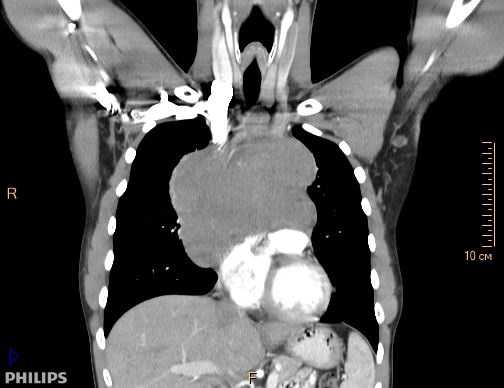

Рисунок 1в. Компьютерная томография пациента К, 31 лет с медиастинальным образованием (НМИЦ онкологии им. Н.Н. Петрова), фронтальная плоскость.

При поражении органов средостения рентгенологическая и клиническая картина неспецифичны (рис.1), только развернутый гистологический диагноз позволяет определиться с тактикой и подобрать эффективную терапию.

КТ ОГК. Объемное образование в средостении (патологически измененный лимфоузел), подтвержденная лимфома.